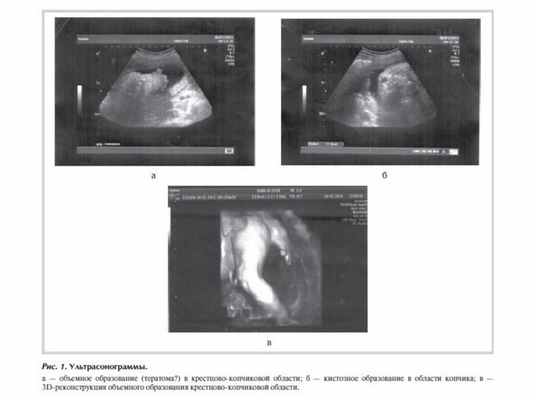

Ребенок от первой беременности после экстракорпорального оплодотворения. Беременность протекала с угрозой прерывания в I триместре, по поводу чего мать получала стационарное лечение. На сроке беременности 29 нед по данным УЗИ поставлен диагноз: врожденный порок развития - тератома, кистозное образование в области копчика (рис. 1). Родоразрешение на сроке гестации 39 нед путем кесарева сечения. Масса при рождении 3050 г, окружность головы 34 см, окружность груди 32 см, рост 50 см. Оценка по шкале Апгар 7/7.

В первые часы жизни ребенок доставлен в отделение реанимации и хирургии новорожденных НИИ детской хирургии НЦЗД РАМН. Проведена компьютерная томография (КТ) с внутривенным контрастированием и магнитно-резонансная томография (МРТ) пояснично-крестцового отдела позвоночника. Данные МРТ: в крестцовом отделе позвоночника имеется четыре позвонка на уровне позвонков SII-SIV, позвоночный канал деформирован, отсутствуют остистые отростки позвонков, имеется дефект канала на уровне позвонка SII, через который пролабируют оболочки спинного мозга. Размер грыжевого выпячивания 14×14×9 мм, содержимое - спинномозговая жидкость (рис. 2).